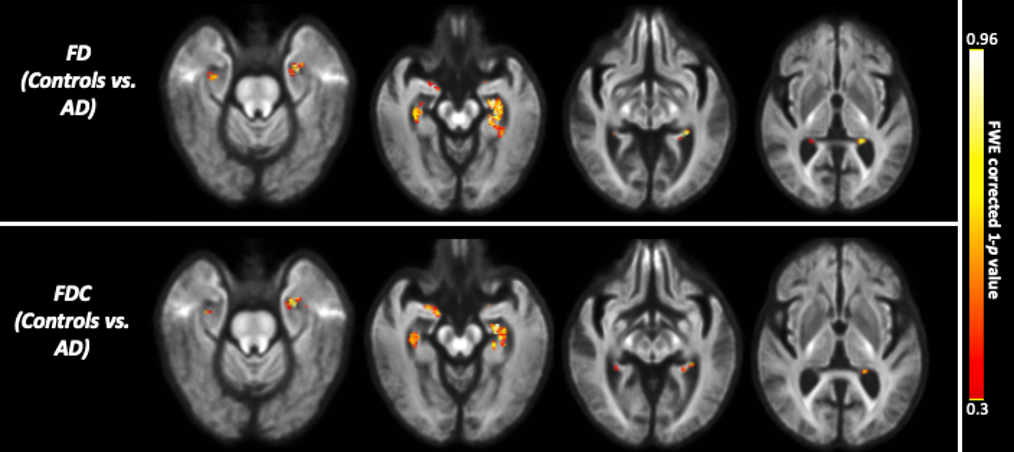

The whole-brain FBA showed significant reduction in FD in individuals with AD compared to MCI, in regions including splenium of corpus collosum, fornix, and the left uncinate fasciculus. Furthermore, AD showed significant reduction in FD in the left uncinate fasciculus compared to controls. Figure 2 shows WM tracts where significant (FWE corrected p <0.05) reductions in FD were observed.We observed subtle reduction in FD and FDC metrics (although the differences were not statistically significant after FWE corrections) in regions including corpus callosum (bilaterally), forceps majors (bilaterally), and uncinate fasciculus in AD compared to MCI. The reduction in FD was more pronounced compared to the reduction in FDC (Figure 3).Furthermore, FD and FDC were observed to be reduced (although not statistically significant after FWE correction) in regions including uncinate and the arcuate fasciculus (bilaterally) in AD relative to controls (Figure 4). We did not observe notable difference in FC in any groups. There were no reductions in FBA measures in MCI relative to controls.

Figure 3: Fibre tract-specific reductions in AD compared to MCI from whole-brain FBA. The white matter regions showing subtle (statistically not significant after FWE correction) to significant reductions in FD, and FDC are superimposed onto the population template.